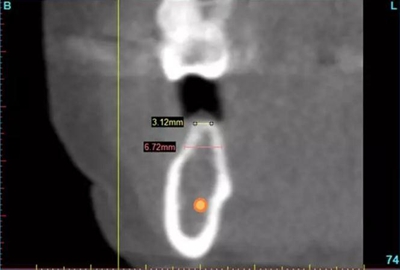

圖3a.右下第一磨牙無牙區(qū)位點術(shù)前和骨增量術(shù)后CBCT掃描。術(shù)前掃描顯示牙槽嵴頂水平骨寬度3.1mm

圖3b. 術(shù)后5個月,在無牙牙槽嵴的不同水平上達到2-5mm 的水平骨增量

術(shù)后3個月,右側(cè)第一磨牙的空間約為9mm(3個月中增加了1.6mm),逐漸接近了對側(cè)第一磨牙的空間(也約9mm)(圖6a)。術(shù)后7個月的錐束CT顯示,右側(cè)第一磨牙區(qū)域獲得了2.5mm的水平骨增量(圖6b 和c)。左側(cè)第一磨牙的無牙區(qū)保持相同的尺寸,在種植體植入前也需要骨增量。

圖6b. 術(shù)前CBCT掃描顯示牙槽嵴寬度僅為5.6mm

圖6c. 術(shù)后7個月時的CBCT顯示,獲得了2.5mm的水平骨增量